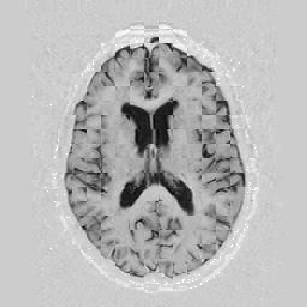

I later attempted 10 iterations at level 2, then 2 iterations at level 1, and 1 iteration at the finest level. Visual results can be seen in Figure [*].

Figure: Multi-scale NRR. From left to right, top then bottom: before NRR; after 10 iterations of NRR at level 2; after another 2 iterations of NRR at level 1; after 1 iteration at level 0.